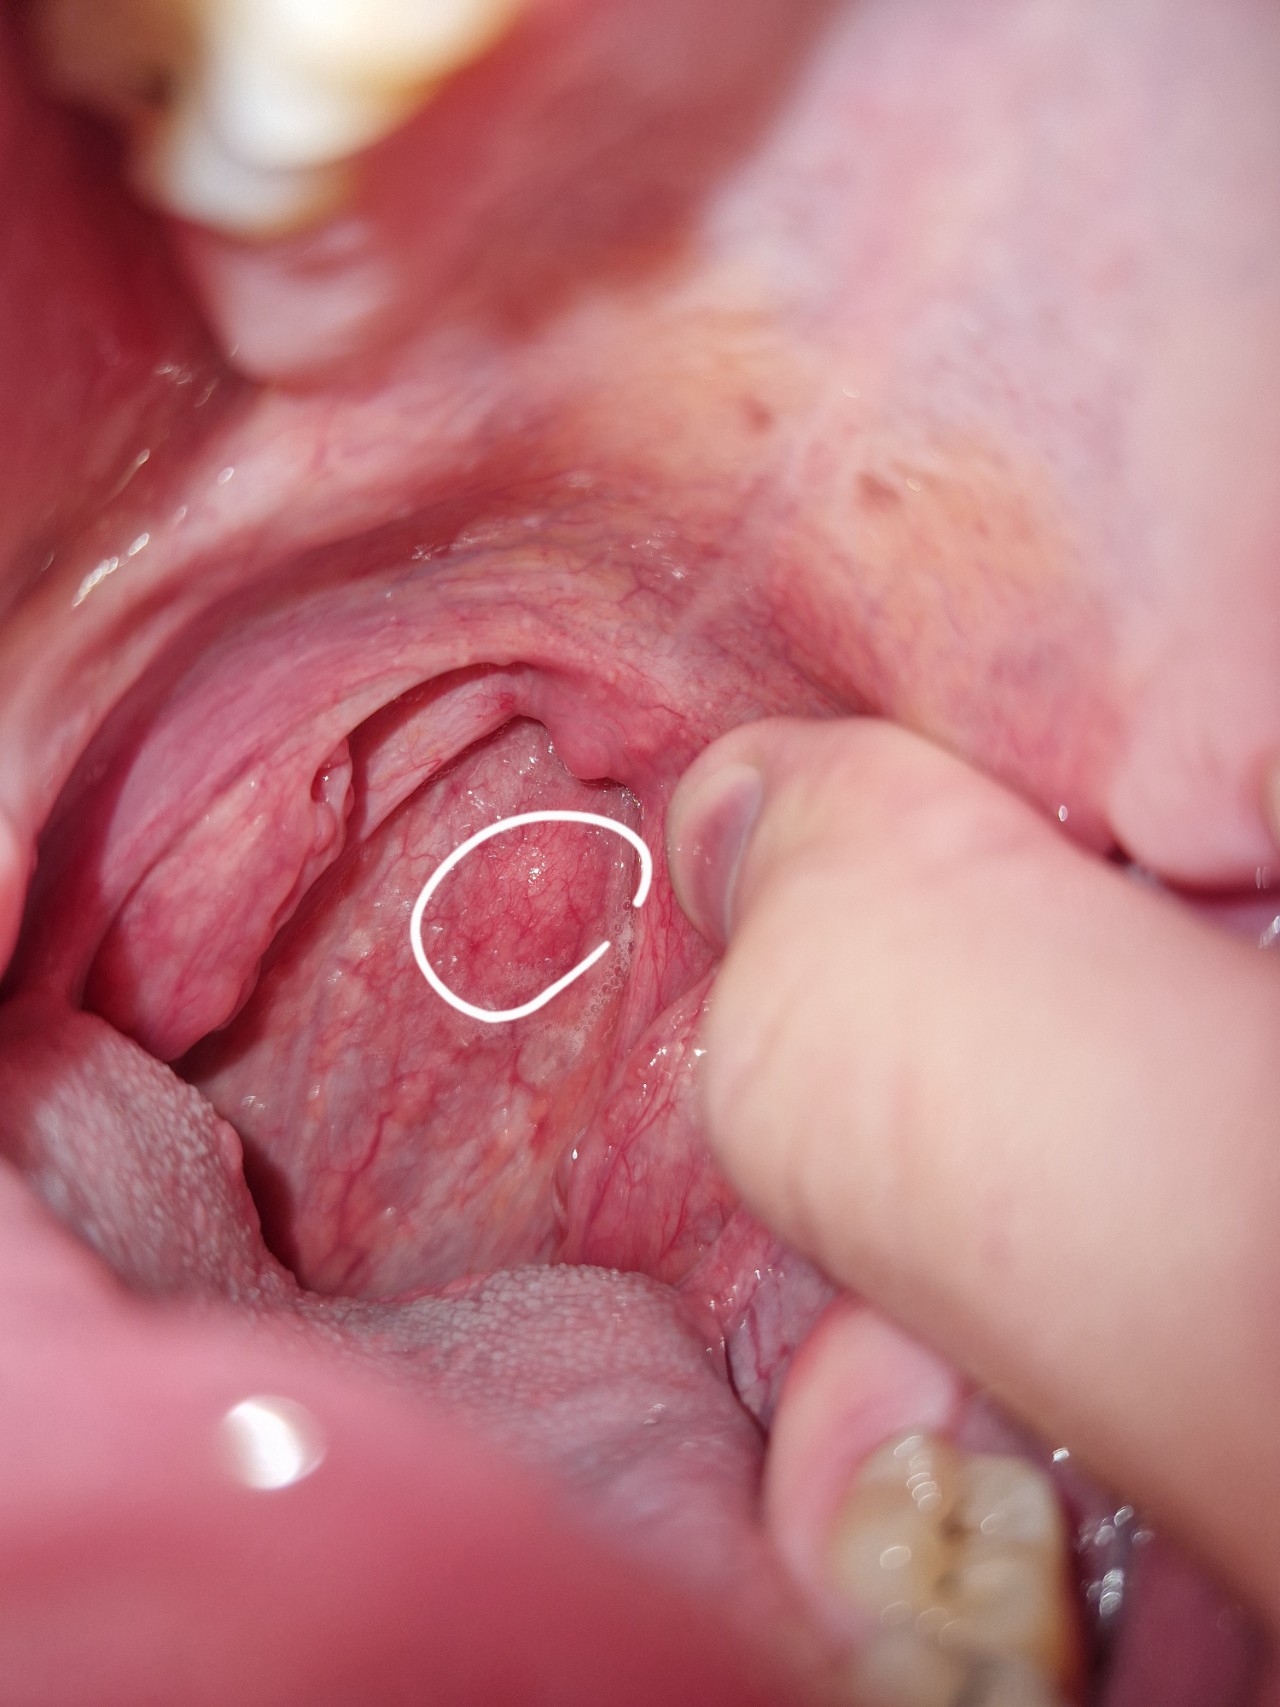

Плотное образование в ротоглотке

Здравствуйте, сегодня впервые заметил образование в области горла (визуально — на задней стенке глотки/вблизи небной дужки). На ощупь оно кажется плотным и неподвижным.

Не могу сказать, как давно оно появилось — раньше не обращал внимания. Не знаю, увеличивается ли оно и меняется ли по форме.

Боли нет, дискомфорта практически не ощущаю. Кровоточивости не было. Язв или повреждений визуально не вижу. Глотание не нарушено, голос не изменился. Слух без изменений.